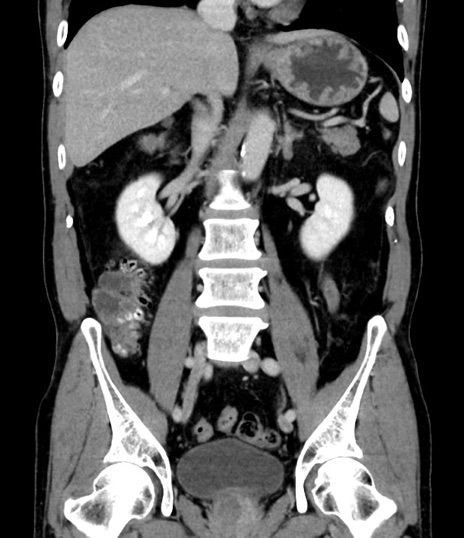

症例8(冠状断像)

【症例】 60歳代男性

【主訴】 黒色吐物

【現病歴】 4日前から嘔気自覚、2日前の朝食後にも嘔気あり、自分で手で嘔吐反射起こし嘔吐したところ血が混ざっていたため受診。

【既往歴】 5年前汎発性腹膜炎を伴う急性虫垂炎で手術、高血圧、前立腺肥大症、高脂血症

【身体所見】 腹部正中に手術癩痕あり 腹部平坦・軟圧痛なし膨満感あり

【データ】WBC 8400、CRP 4.54